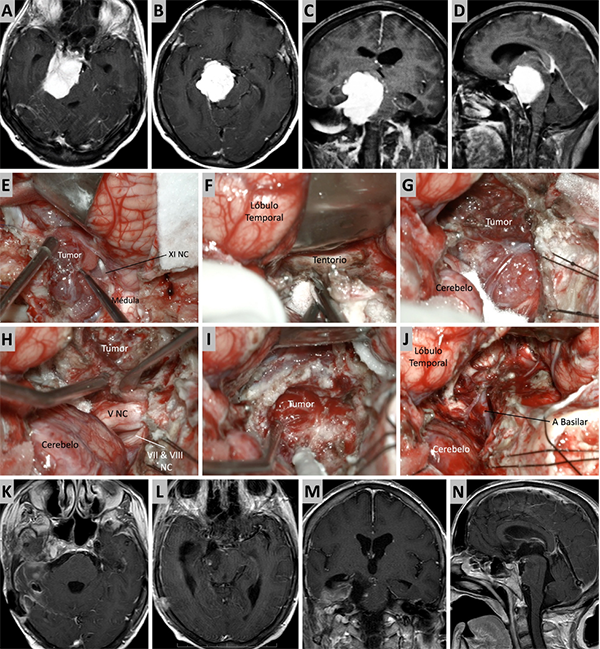

Figura 7. Caso ilustrativo #5. Resonancia que muestra MRPC con implantación petroclival y extensión a la fosa media. Paciente con audición conservada. A-D. Se presentan las imágenes prequirúrgicas, corte axial, coronal y sagital. E. Se realizo un abordaje presigmoideo combinado con un abordaje subtemporal. Se logro una visión directa del tumor, desde la región del clivus medio hasta la fosa media. F. Se observa una resección tumoral del clivus medio y fosa media casi total. G. Lesion tumoral en clivus medio. H-J. Resección casi total del tumor. La retracción del lóbulo temporal fue necesaria para tener mayor visibilidad de la incisura tentorial. K-N. RMN posquirúrgica donde se observa una resección quirúrgica casi total.

Figura 8. Caso ilustrativo #6. Resonancia que muestra MRPC con implantación petroclival y extensión a la fosa media. A-D. Se presentan las imágenes prequirúrgicas, corte axial, coronal y sagital. E-J. Se realizo un abordaje presigmoideo combinado con un abordaje subtemporal, logrando una exposición del seno sigmoideo y una visión directa del tumor consiguiendo una resección total. K-M. RMN posquirúrgica donde se observa una resección quirúrgica total.